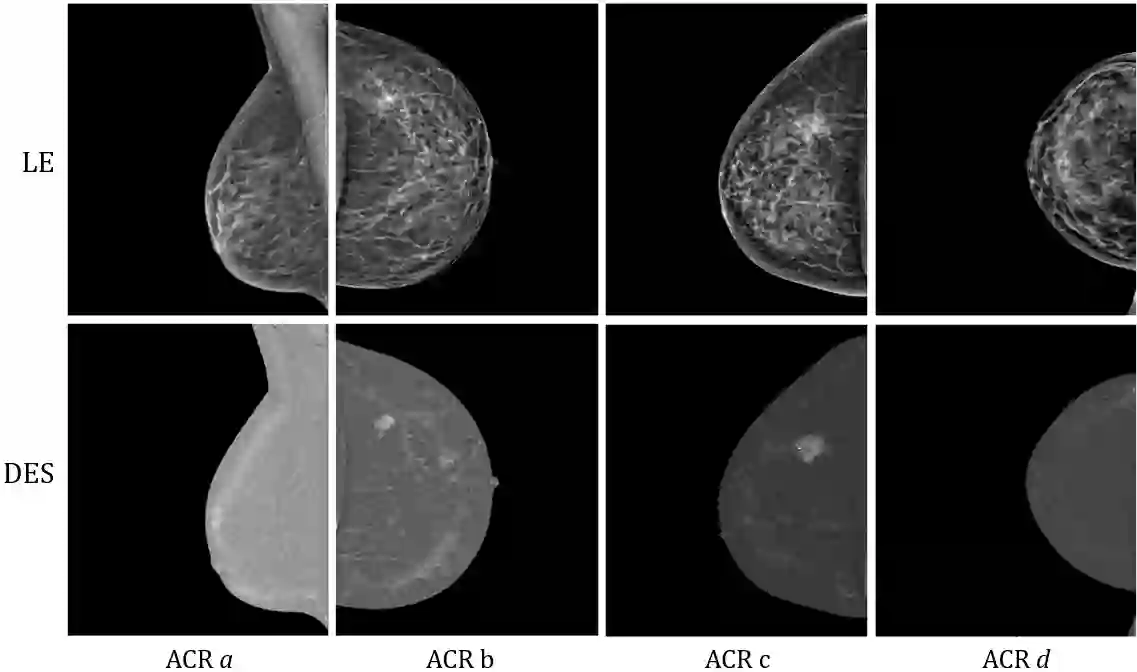

Contrast Enhanced Spectral Mammography (CESM) is a dual-energy mammographic imaging technique that first needs intravenously administration of an iodinated contrast medium; then, it collects both a low-energy image, comparable to standard mammography, and a high-energy image. The two scans are then combined to get a recombined image showing contrast enhancement. Despite CESM diagnostic advantages for breast cancer diagnosis, the use of contrast medium can cause side effects, and CESM also beams patients with a higher radiation dose compared to standard mammography. To address these limitations this work proposes to use deep generative models for virtual contrast enhancement on CESM, aiming to make the CESM contrast-free as well as to reduce the radiation dose. Our deep networks, consisting of an autoencoder and two Generative Adversarial Networks, the Pix2Pix, and the CycleGAN, generate synthetic recombined images solely from low-energy images. We perform an extensive quantitative and qualitative analysis of the model's performance, also exploiting radiologists' assessments, on a novel CESM dataset that includes 1138 images that, as a further contribution of this work, we make publicly available. The results show that CycleGAN is the most promising deep network to generate synthetic recombined images, highlighting the potential of artificial intelligence techniques for virtual contrast enhancement in this field.